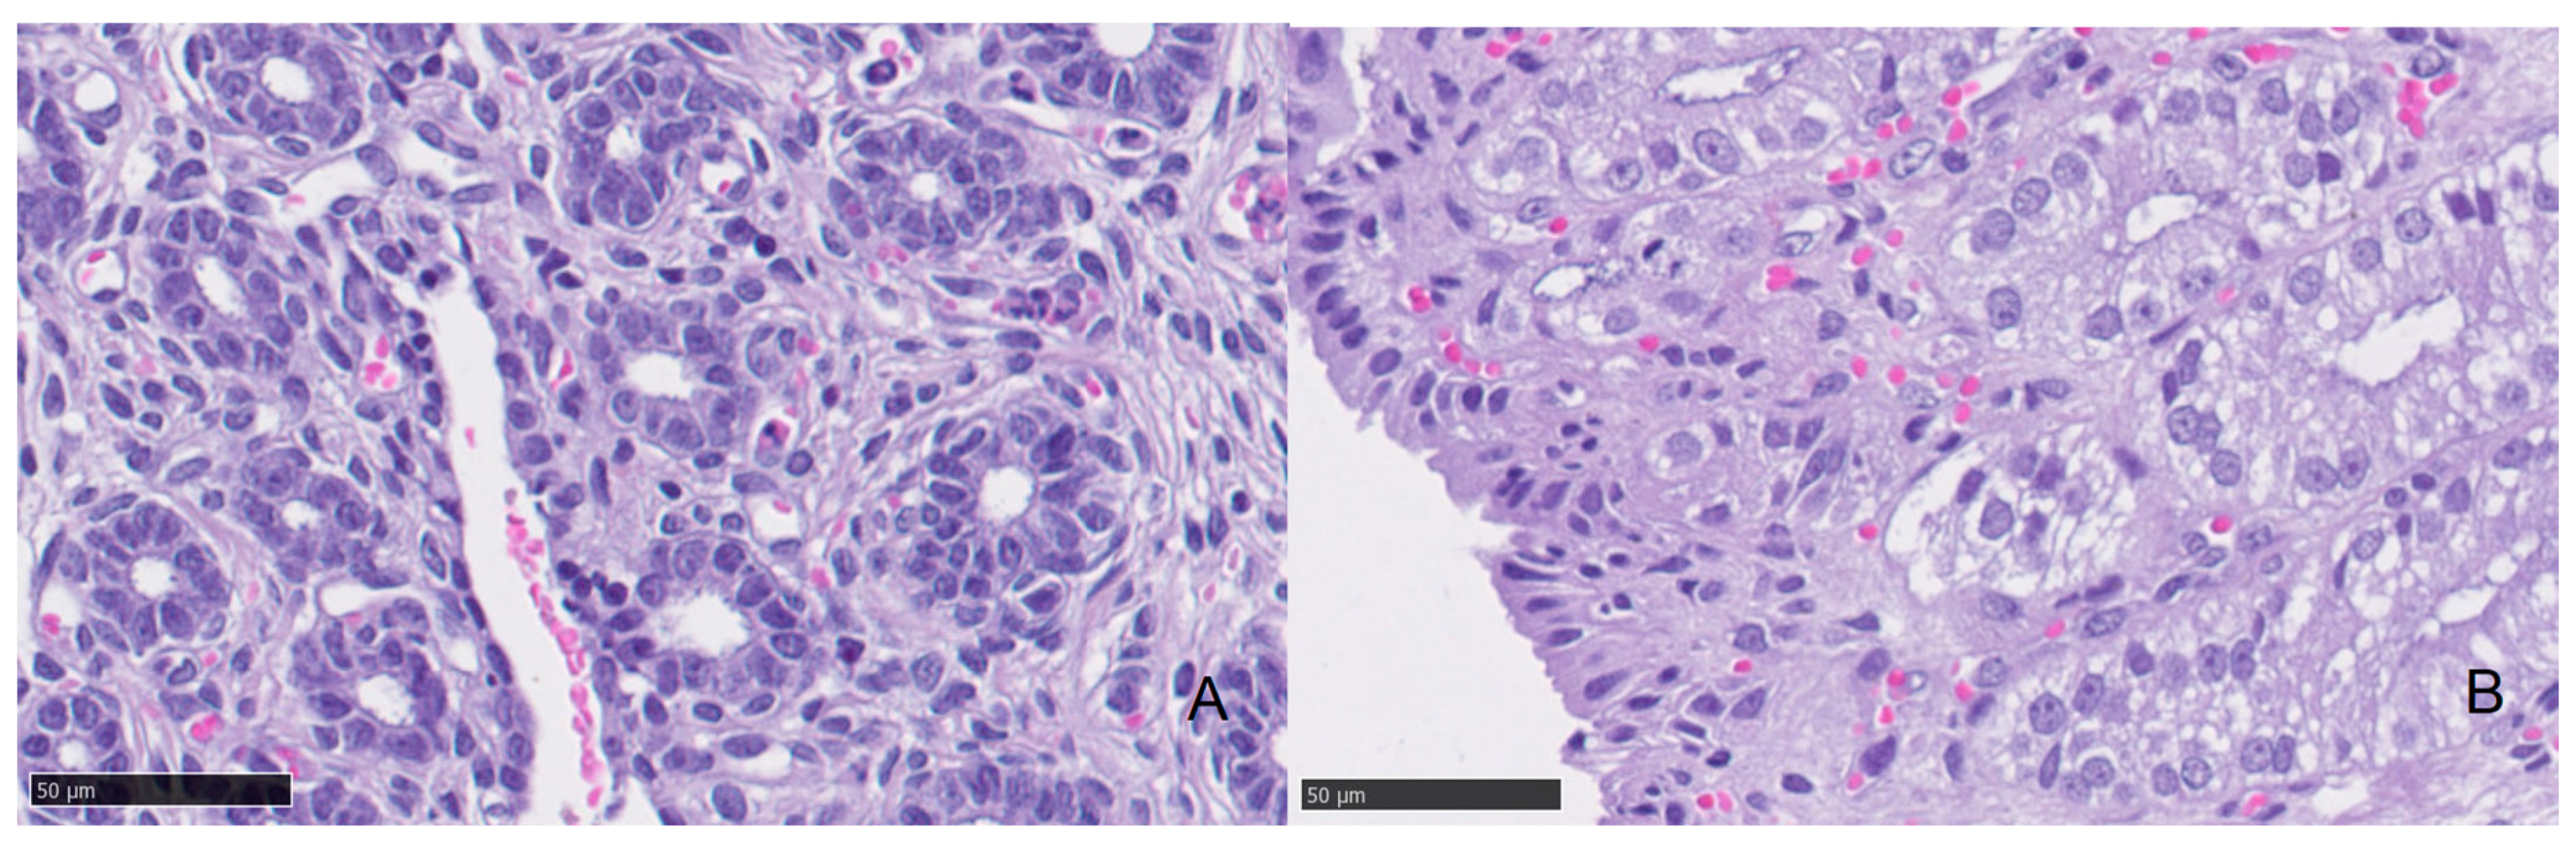

3.3. Histology

| Low Progesterone | High Progesterone | ||||||

|---|---|---|---|---|---|---|---|

| Median | Minimum | Maximum | Median | Minimum | Maximum | p | |

| Epithelial Height (cm) | 7.95 | 5.22 | 11.40 | 15.23 | 6.36 | 31.22 | 0.000 |

| Diameter 1 (cm) | 53.99 | 28.03 | 89.47 | 86.97 | 40.00 | 158.33 | 0.039 |

| Diameter 2 (cm) | 37.67 | 22.33 | 54.57 | 53.04 | 23.39 | 90.36 | 0.039 |

| Mean Diameter (cm) | 45.82 | 25.18 | 68.74 | 70.00 | 36.10 | 124.35 | 0.012 |

| Glandular Density (glands/400×) | 6.12 | 0.95 | 11.40 | 7.49 | 0.50 | 18.20 | 0.278 |

| Neutrophil (in 10 fields 400×) | 0.49 | 0.00 | 4.60 | 0.16 | 0.00 | 0.60 | 0.053 |